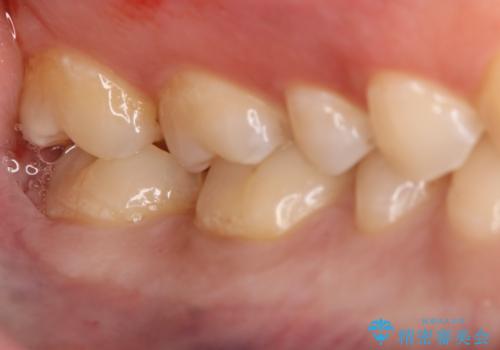

- 右下6・7番の治療のやり変えを主訴に来院された患者様です。

保険の材料が劣化し中で虫歯が進行しているため、古い材料と虫歯を全て除去した上で詰め直す必要がありました。

切削量・形態を考慮し、セラミックインレーでの治療を計画しました。